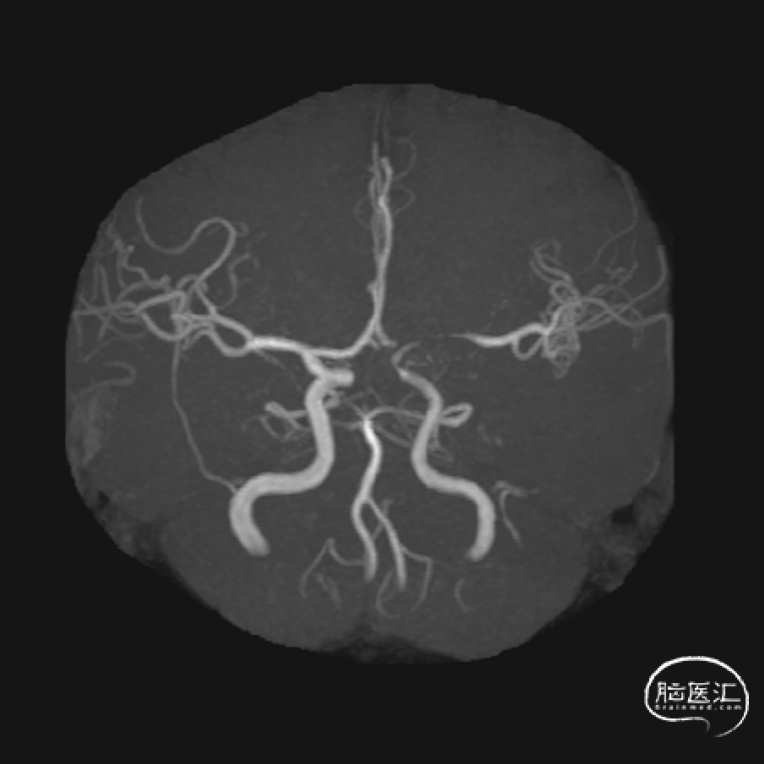

一期术后1月再次来院复查,MRA提示瘤颈复发。

工作位DSA提示瘤颈复发,决定行血流导向装置植入术。

术后3月MRA:瘤颈处血流信号较术前减少。

术后6月MRA:载瘤动脉通畅,动脉瘤不显影。

术后2年MRA:动脉瘤无复发。